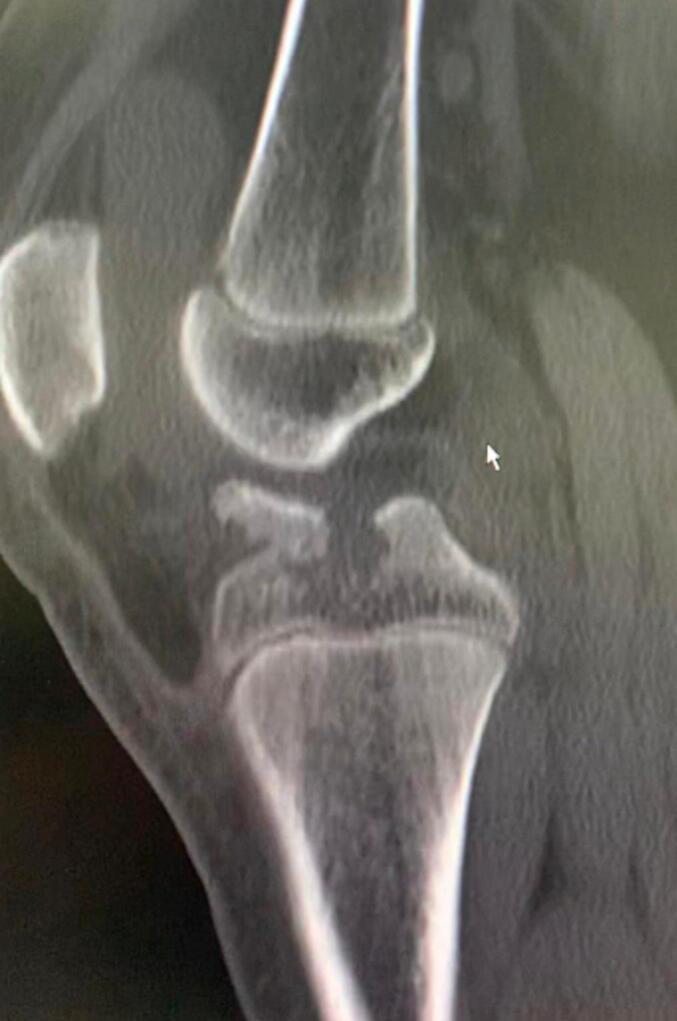

Distal anterior cruciate ligament avulsion from tibial side is an unusual injury. It can be either bony avulsion, which is more common, or rarely a soft tissue peeling of tibial spine with no bone injury. This case report represents a very infrequent injury of combined soft tissue peeling of distal anterior cruciate ligament along with bony avulsion of tibial spine in a 12-years-old boy after falling from his bike.

前交叉韧带从胫骨侧远端撕脱是一种不常见的损伤。它可以是较为常见的骨性撕脱,或者极少情况下是胫骨棘的软组织剥离且无骨质损伤。本病例报告呈现了一名12岁男孩从自行车上摔下后,前交叉韧带远端合并软组织剥离及胫骨棘骨性撕脱这种非常罕见的损伤情况。